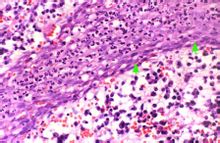

根尖肉芽腫病理分析根尖肉芽腫為附著在牙根尖部約綠豆大小的肉芽,因與牙根尖區牙周膜相連,可隨拔牙時一同拔出(圖2)。 鏡下觀察根尖區可見增生的肉芽組織團塊,周界清楚,主要由新生的毛細血管、成纖維細胞和浸潤的各類炎症細胞構成,炎症細胞包括淋巴細胞、漿細胞、巨噬細胞和中性粒細胞(圖3,4)。毛細血管內皮細胞增生腫脹,巨噬細胞吞噬脂質後形成泡沫細胞。可見含鐵血黃素和膽固醇晶體沉積。膽固醇晶體在製片過程中被有機溶劑溶解而呈現針狀透明裂隙,並可引起多核巨細胞反應。 肉芽組織外周常有纖維結締組織包繞。根尖牙骨質和牙槽骨有吸收(圖5)。 根尖肉芽腫內可見增生上皮團或上皮條索,相互交織呈網狀(圖6,7),這些上皮來源於:(1)Malassez上皮剩餘;(2)經竇道口長入的口腔上皮; (3)牙周袋袋壁上皮; (4)來自呼吸道上皮,此見於病變與上頜竇相通的病例。